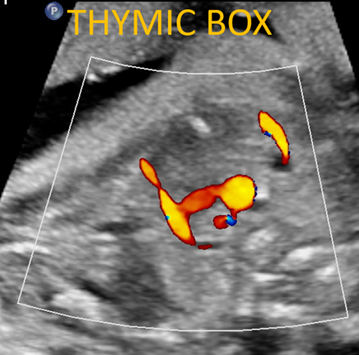

This course covers techniques for studying the fetal heart by ultrasound, including normal appearances and pathological findings. Radiologists and obstetrician-gynecologists familiar with fetal ultrasound will find this course useful for improving their fetal heart assessment skills

This course provides an orientation to first-trimester screening, including nuchal translucency, nasal bone assessment, tricuspid regurgitation, risk calculation, etc